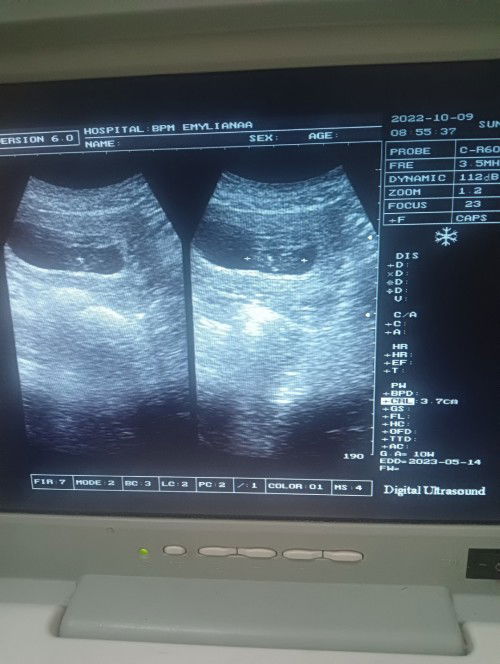

Selasa kemarin aku USG pas 9week dan belum terlihat janin, hanya kantung dan ukurannya kecil. Kata dokter kemungkinan besar hamil BO dan di suruh nunggu dlu seminggu atau 2 Minggu untuk kontrol lagi. Besoknya setelah USG keluar flek coklat hanya sedikit sekali menempel di CD dan setelah itu udah gak ada flek lagi. Kondisi ku sekarang masih mual, masih ngerasain gejala hamil. Apakah hamil BO emang gitu ya? Flek emang sedikit? Trus kapan bagusnya ke dokter? Apa harus nunggu seminggu? Atau langsung ke RS aja? Soalnya flek sedikit sekali dan hanya keluar sekali#seriusnanya #bantusharing